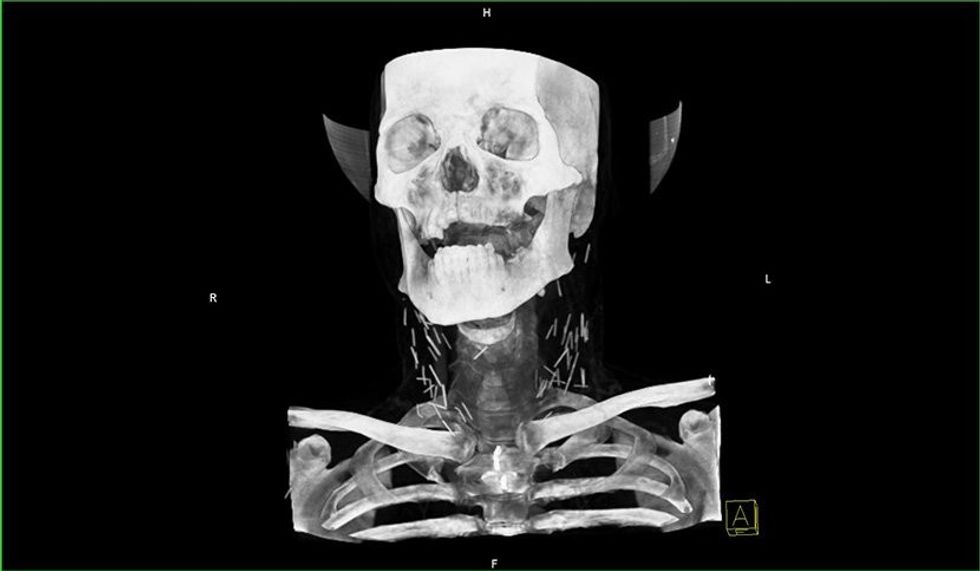

Fotografia e rëntgenit me rreze x ka nxjerr në pah dhjetëra gjilpëra të thyera në qafën e tij, ndërsa pas rekonstruimit të fotografisë në versionin 3D nga radiologët, është konstatuar se vërtetë bëhet fjalë për dhjetëra gjilpëra.

Mjekët besojnë se ky narkoman i cili sipas të gjitha gjasave nuk kishte pasur ku të shpohet në duar, dhe kështu kishte injektuar heroinën në venat e qafës.